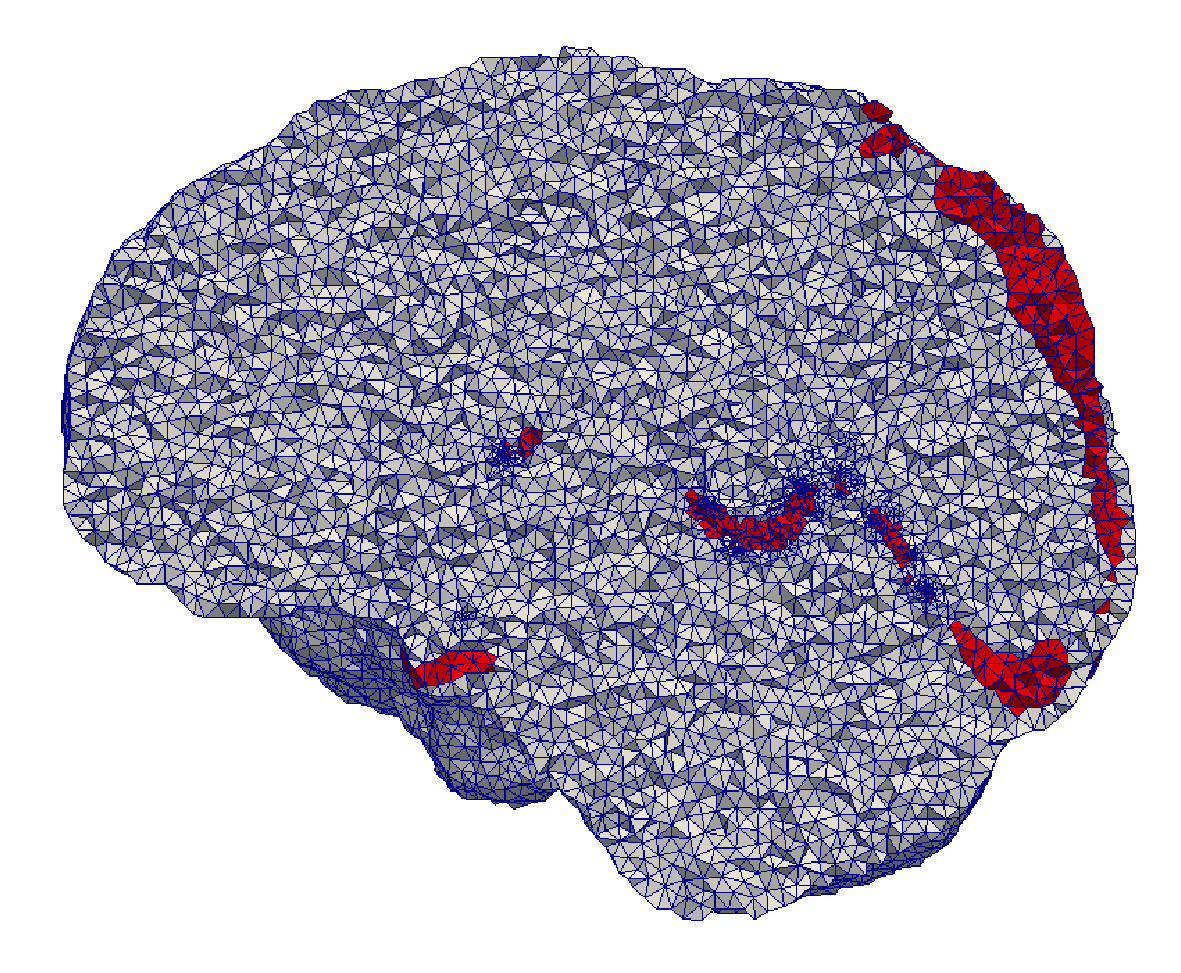

An iterative solver is employed [57] to solve the system. A linear assumption is made for the material stiffness and the displacements of the biomechanical model. Once U𝑈U has been found, the mesh is updated by adding the computed displacements to the current coordinates of the vertices, and the procedure is repeated until the iterations reach a maximum number. Figure 13 illustrates an example of the procedure.

Refer to caption

(a)

(b)

(c)

(d)

(e)

(f) HD0=1.79subscriptHD01.79\text{HD}_{0}=1.79 mm

(g) HD3=1.31subscriptHD31.31\text{HD}_{3}=1.31 mm

(h) HD7=0.96subscriptHD70.96\text{HD}_{7}=0.96 mm

(i) HD10=0.91subscriptHD100.91\text{HD}_{10}=0.91 mm

Figure 13: Nidus mesh during deformation with 10 iterations. The figure on the top depicts the extracted source (green) and target (red) points used for deformation. Each column depicts the deformed mesh and an intersection between the mesh surface and the image plane at iterations i=0,3,7,10𝑖03710i=0,3,7,10 (from left to right). HDisubscriptHD𝑖\text{HD}_{i} denotes the mesh fidelity in terms of a Hausdorff Distance metric, at iteration i𝑖i. The smaller the HD value, the higher the fidelity. As the number of iterations advances, the mesh exhibits a smoother surface.